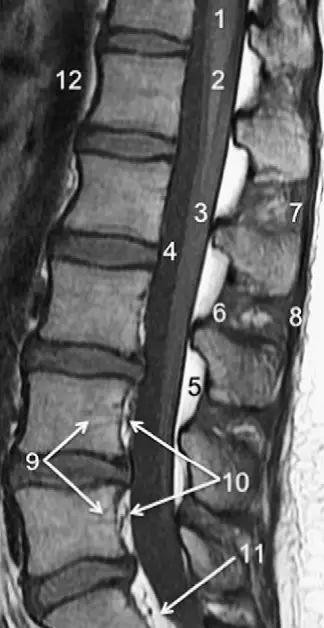

图 3 腰椎矢状位 T1WI 序列成像:1,脊髓;2,脊髓圆锥;3,马尾;4,蛛网膜下腔;5,硬膜外脂肪;6,黄韧带;7,棘间韧带;8,棘上韧带;9,椎体静脉丛;10,硬膜外静脉丛;11,硬膜外脂肪;12 主动脉